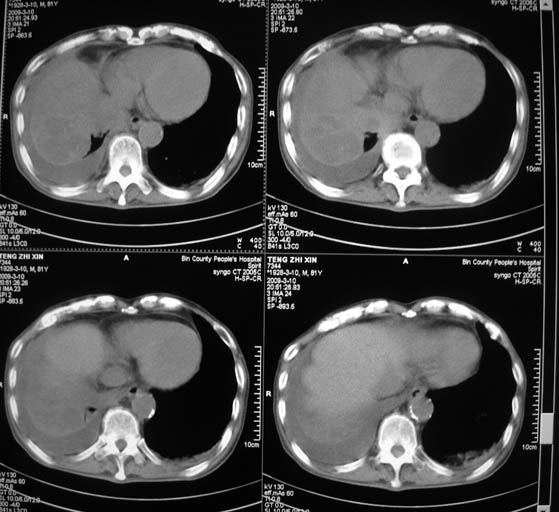

标题: CT18642:男,81岁,发热待查。

男,81岁,发热待查,右侧是占位还是膈疝?

右肺中央型肺癌并两侧胸水,左肺转移,腹水

1)考虑右肺下叶中央型肺癌并左肺转移。2)两肺上叶结核(陈旧性)。3)双侧胸腔积液。4)腹水。

右中央型肺癌并双肺及胸膜、肝脏转移

右中心型肺癌并双肺及胸膜、肝脏转移!

右肺中心型肺癌,胸、腹水